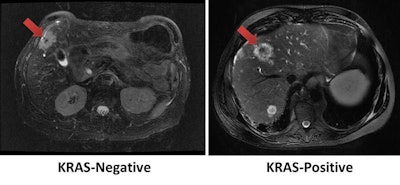

Using tumor radiomic features on MRI, a machine-learning model correctly identified the KRAS mutation status of a KRAS-negative tumor (left) and KRAS-positive tumor (right). Images courtesy of Dr. Dania Daye, PhD.For each patient, the largest hepatic lesion was identified on the portal venous phase T1-weighted fat-suppressed contrast images and manually segmented. The multiparametric radiomic vector was then extracted from each lesion. A total of 52 radiomic features were extracted from each lesion: 20 tumor morphologic features, 15 Laws texture features, 14 Haralick's texture features, and three Tamura texture features.